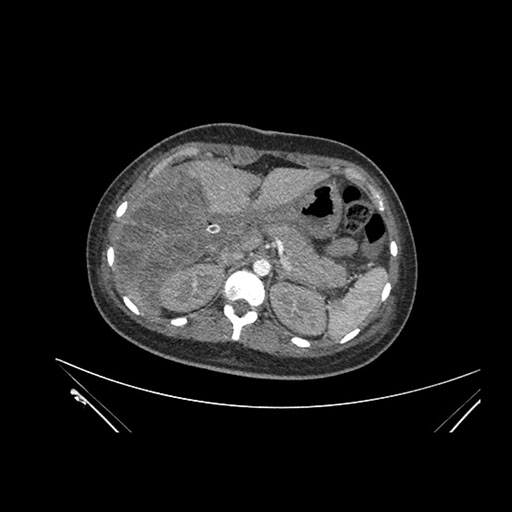

Imaging Analysis

Look through the patient's CT scan to identify any areas of concern for the necessary procedure.

Coronal Venous

Based on initial findings, which issue(s) would you be most concerned about?